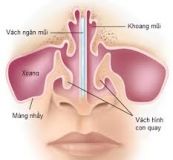

Lệch vách ngăn mũi nếu không được điều trị có thể gây ra chảy máu cam, viêm xoang tái phát. Hiểu hơn về triệu chứng bệnh để có phương pháp chẩn đoán và điều trị hiệu quả với bài viết dưới đây.

Gãy sống mũi là tình trạng gãy xương mũi. Trong hầu hết trường hợp, tình trạng gãy xương mũi cũng làm tổn thương sụn mũi và vách ngăn mũi. Cùng eLib.VN tìm hiểu bài viết dưới đây để hiểu rõ hơn nhé!